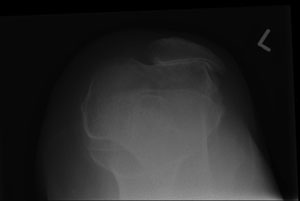

Figure 1: X-ray of the left knee showing medial compartment arthritis

This is the most commonly affected compartment in the knee; one third of patients will have isolated medial compartment arthritis (see fig 1).